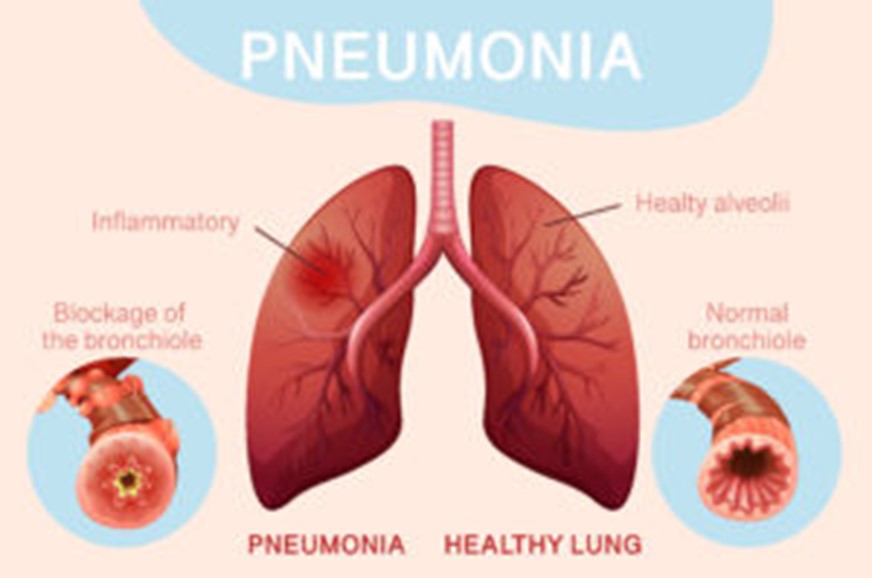

Hippocrates (460–370 BC) was the first to describe pneumonia (1). Pneumonia is a lung illness caused by some microorganisms. Pneumonia is an infection of the pulmonary parenchyma caused by various organisms. It’s a lung infection caused by an acute respiratory tract infection (ARTI). When a person gets pneumonia, the alveoli in their lungs get clogged with pus and fluid, making breathing difficult and restricting oxygen intake (2).

Many attempts have been made to define pneumonia based on the etiology, clinical environment in which the patient contracted the infection, and pattern of lung parenchyma involvement, among other factors (2).